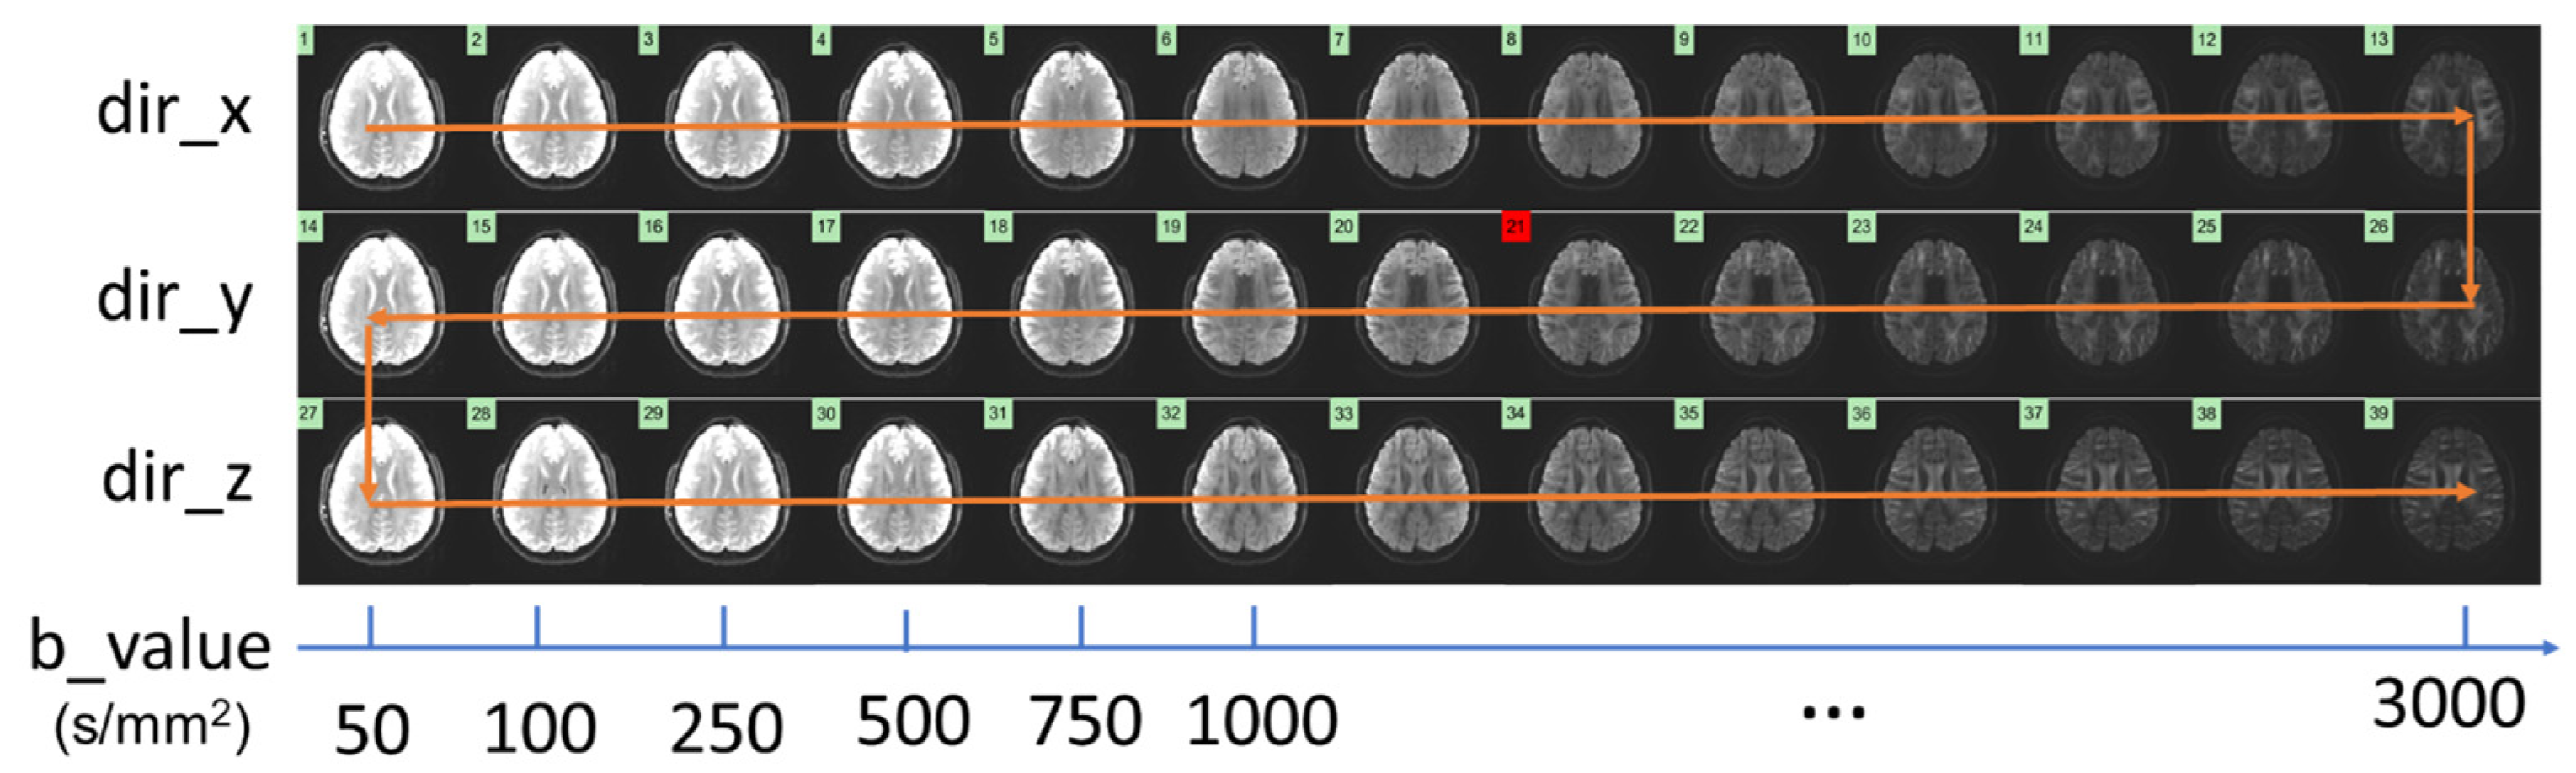

2.2. Data Acquisition and Image Reconstruction